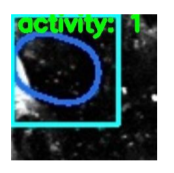

3. Furthermore, once the frames were extracted from the videos, these images were cropped to train the classifier. Regions of blood flow and stalled vessels were randomly cropped from the extracted frames.

4. This exercise was performed to train the classifier in a more efficient way by omitting the unnecessary parts and extracting the necessary data from the images.

5. The above images where then classified using four distinct architectures viz. Resnet50, Resnet101, Resnet152 and AlexNet. The logic that is used in the classification is that in case when blood is actually flowing through the vessel a luminescent spot is picked up by the algorithm whereas in case when the blood is not flowing or stalled a black spot can be observed. So when we are looking at images of a non Alzheimer individual the frequency of these bright luminescent spots would be higher as compared to the black spots and vice versa for an Alzheimer infected person. Whichever algorithm is able to best pick up this difference will give us the highest accuracy